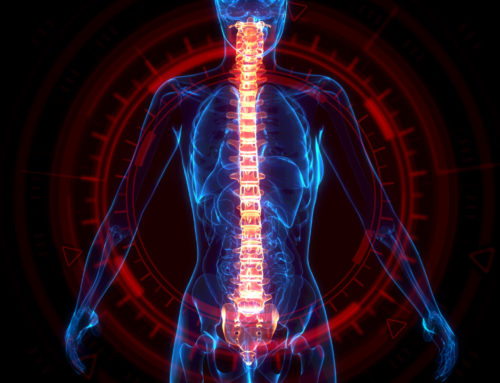

Cervical myelopathy is a condition that commonly affects older US adults.

Compression of the spinal cord in the neck is to blame for the disorder. It can cause debilitating symptoms that may or may not worsen over time. As many as one-quarter of patients will need multiple operations for recurring symptoms.

What Is Cervical Myelopathy?

Cervical myelopathy describes compression on the spinal cord at a cervical level. The surgical condition includes spasticity, pathologic reflexes, clumsiness, and other issues. Many patients experience upper extremity symptoms as a result.

Cervical myelopathy can be treated by a doctor. Surgery decompresses the affected area. Poor prognosis is linked to longer symptomatic duration, reduced range of motion, and being born with female anatomy.